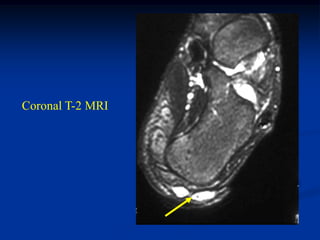

Case #1211.3                        Synovial hemangioma knee

68 year old female with soft mass medial knee for years

Cor T-1    T-2

Gad

Sag PD   Gad

Axial T-2   Gad